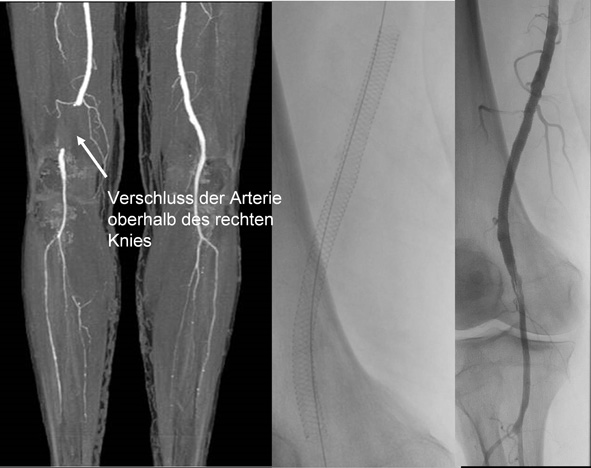

• Arterielle Interventionen (Ballondilatationen, Stentimplantationen)

• Extremitäten